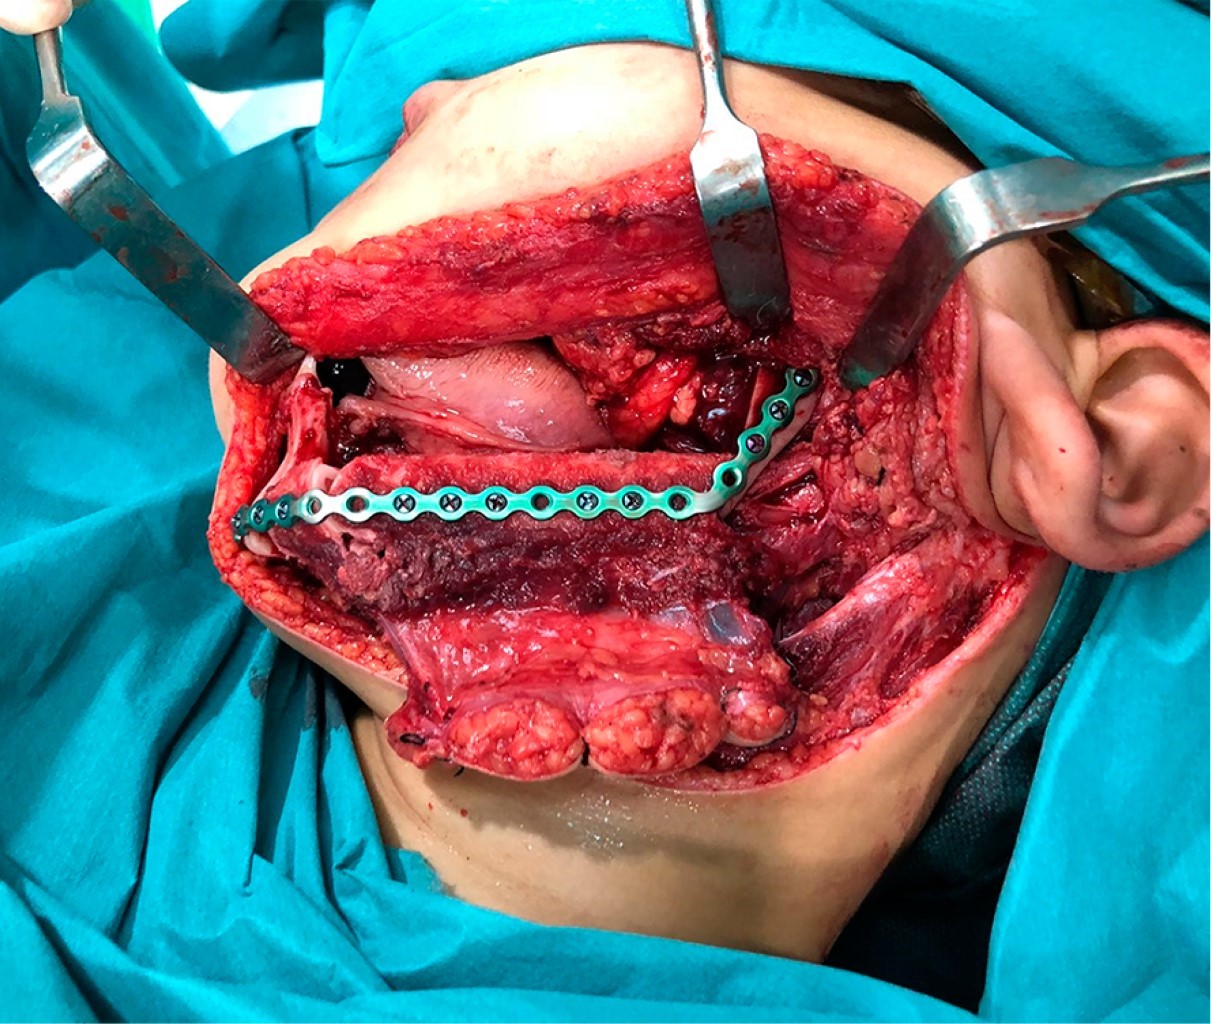

Introduction: Oral cavity squamous cell carcinoma is a frequent entity in adult malignant head and neck pathology; however, it is extremely rare in pediatric age. The treatment and reconstruction of pediatric patients is a challenge due to its high complexity and the few cases described to date in the literature. Material and methods: A clinical case of mandibular squamous cell carcinoma in a pediatric patient is presented. Diagnosis is made by histopathological study and radiological tests, and a virtual planning for mandibular reconstruction is performed. A review of the literature is performed since it is a rare entity. Results: A 9-year-old male of Asian origin came to our office for clinical symptoms of suppuration in the left mandibular region close to the first definitive molar, of approximately 2 months of evolution. A biopsy was performed with an anatomopathological result of squamous cell carcinoma. The case was presented to the Head and Neck Tumors Committee and surgical treatment was decided: left segmental mandibulectomy with oncologic safety margins, left anterolateral functional cervical dissection and reconstruction with microvascularized fibula flap fixed with titanium rod. Cutting guides and virtual planning were used. At 24 months postoperative follow-up there was no locoregional or distant recurrence. Conclusions: Oral cavity squamous cell carcinoma in pediatric age has a low incidence, requiring optimal management and reconstruction. The fibula flap could be the most indicated option for mandibular reconstruction in children. The preservation of the mandibular condyle could favor the mandibular growth of the patient during development.

Figure 2